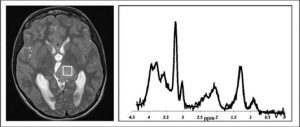

‘Diagnosing brain tumour through functional imaging and deep learning’ Dadi Zhao

Conventional MR (magnetic resonance) imaging is able to provide useful information on the structure, and functional imaging (spectroscopy) can aid getting estimates of certain chemicals (called metabolites) in the tumour. In this project I am trying to find a novel way to realise automatic brain tumour classification through machine learning, in the same exact area of the brain, to better determine which type and grade of brain tumour a patient has.

‘Non invasive identification of medulloblastoma genetic subtypes using metabolite profiles and imaging features’ Sarah Kohe

My main project is funded by Children with Cancer UK and involves the development of rapid and non-invasive methods of identifying the different genetic types of medulloblastoma based on their metabolite (chemical) profiles and the other features that we can see using MRI (Magnetic Resonance Imaging). Finding out how we can diagnose (or identify) these earlier and non-invasively will help doctors better plan treatment, and have more informed discussions with the patient and their family in the crucial early stages after the tumour has been found. Improving our understanding of the metabolite pathways in these different types (or subgroups) of medulloblastoma also means that we might find new ways to treat this.